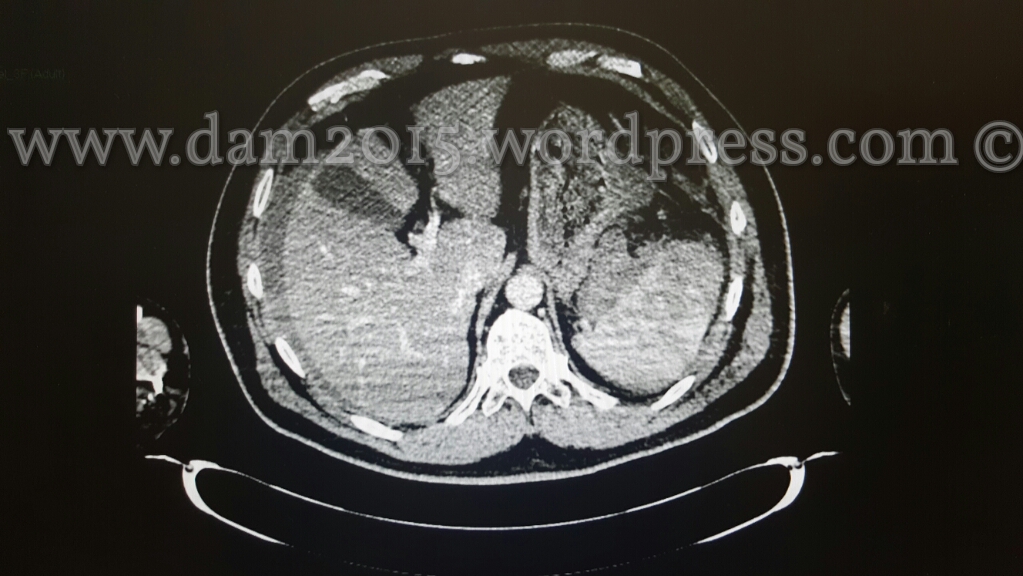

Pz uomo, 56anni.

Incidente stradale moto-auto.

Rottura di milza in due tempi. Emoperitoneo.

Splenectomia.